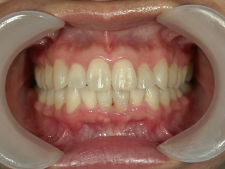

矯正歯科 治療後矯正歯科 プチワイヤー矯正 治療後矯正歯科(プチワイヤー矯正)治療後

41歳女性 浜松市浜北区在住

治療期間 1年3カ月

主訴:下の前歯の歯並びが乱れていて、舌に当たって痛い。

矯正歯科 治療後 ミニインプラントを2本埋入し、下顎前歯を圧下